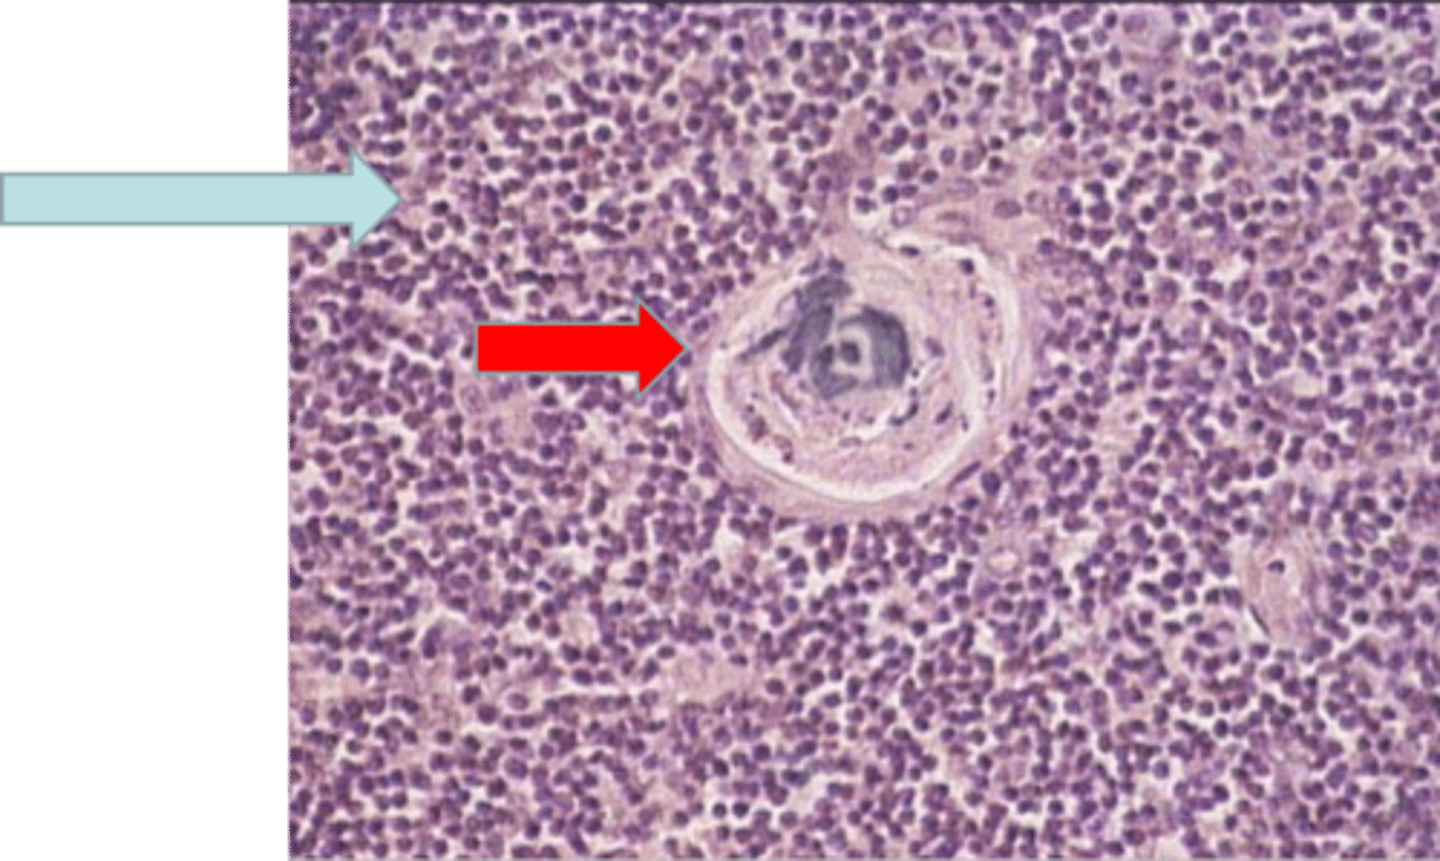

spleen

where is this tissue located?

white pulp

W?

red pulp

R?

PAL

periarteriolar lymphatic sheath

blue arrow

central artery

yellow arrow

Where is this tissue?